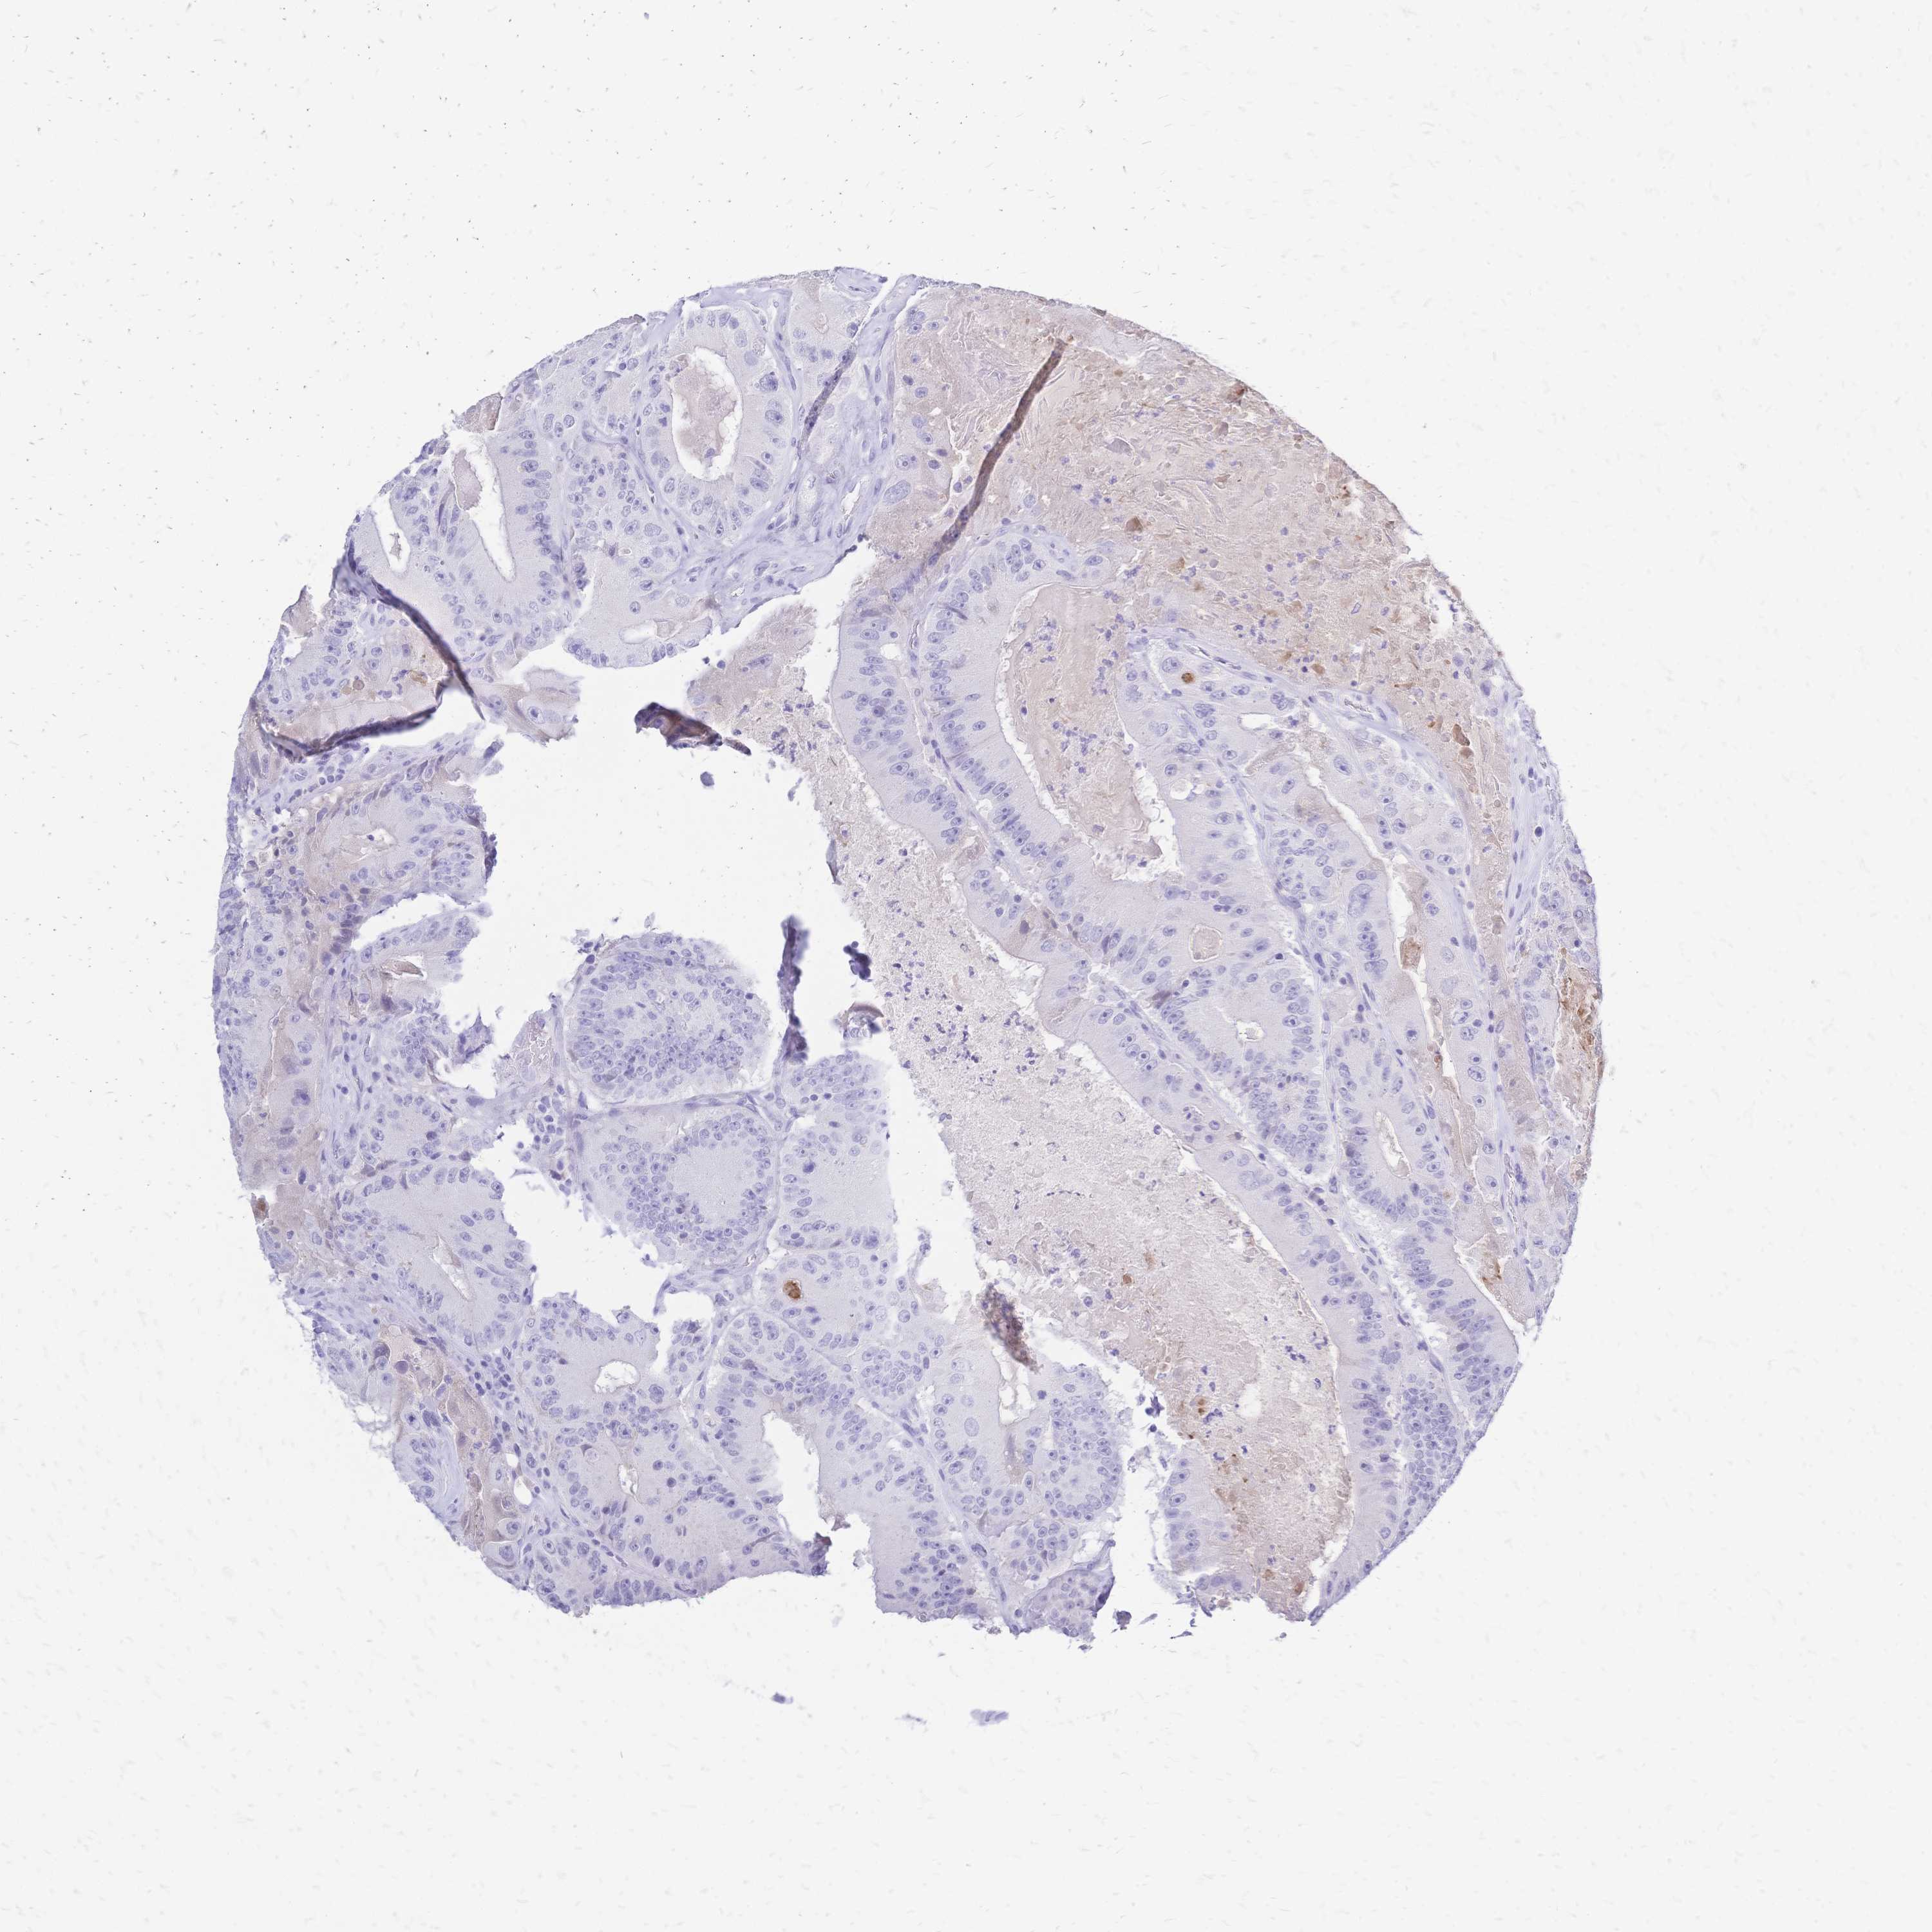

CANCER COLORECTAL CANCER Show tissue menu

Colorectal cancer

Human cancer

Rectum adenocarcinoma